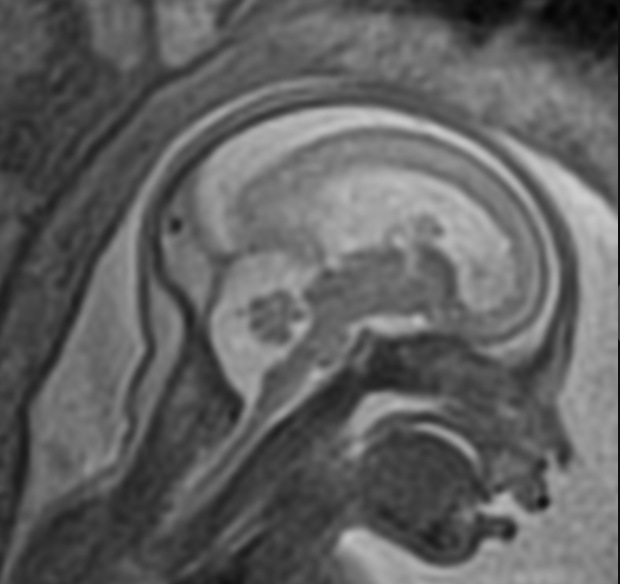

Imagem 1

Complicações neurológicas da Fludarabina